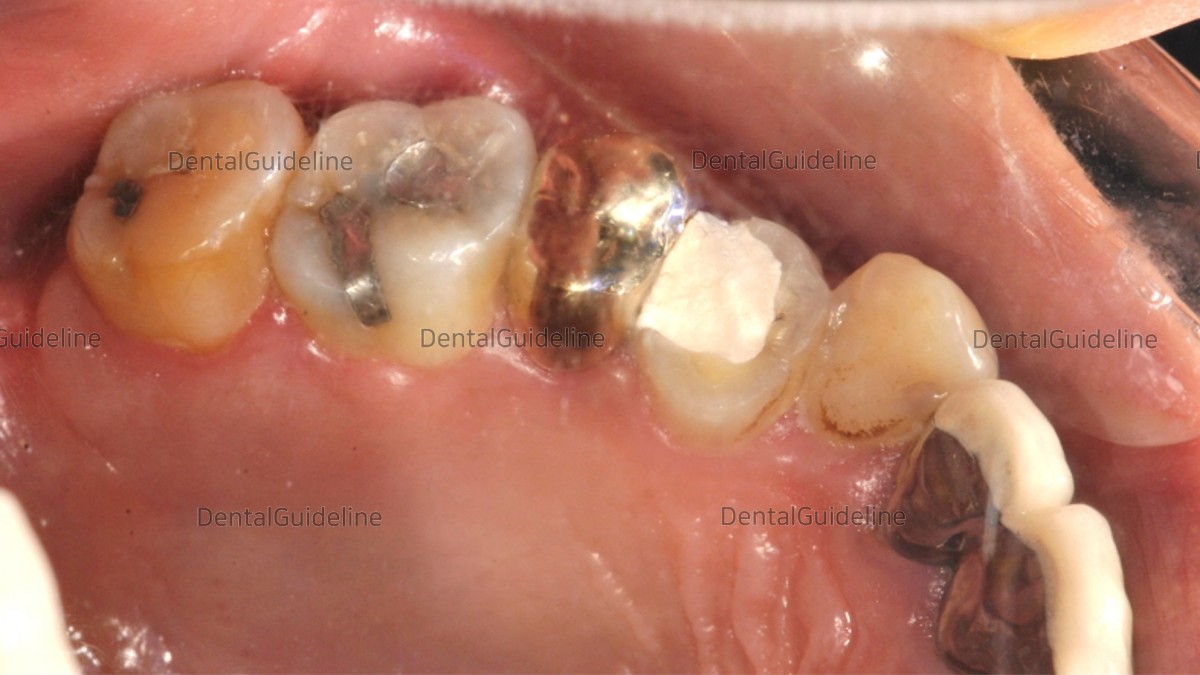

4. A lot of caries has progressed subgingivally, so it is not possible to form a normal prosthetic margin.

5. In the 2nd premolar, when the old crown was removed, caries progressed a lot.